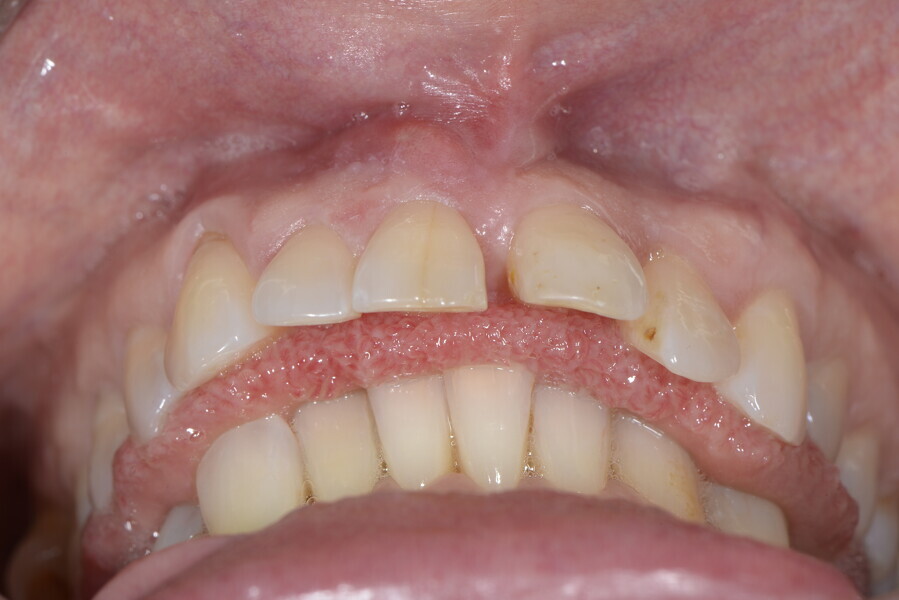

The 58-year-old patient wished to improve his oral aesthetics and function, complaining of mobility of the posterior teeth and wear of the anterior teeth. After data collection, a very complex situation was identified (Figs. 11–13):

1. severe periodontitis with poor prognosis of some teeth;

2. anterior crossbite;

3. severe wear mainly of the anterior teeth and compensatory eruption;38

4. atypical swallowing and lower posture of the tongue at rest;

5. masticatory dysfunction during the mastication test; and

6. no significant signs of temporomandibular disorder.